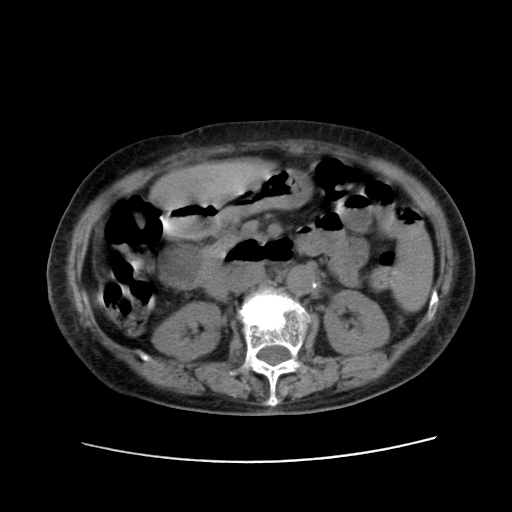

女,77.无不适

肝脏变异、异位胆囊,肝右叶肝内胆管结石并肝内胆管扩张。

肝右叶肝内胆管结石并肝内胆管扩张。

肝右叶肝内胆管结石并肝内胆管扩张

胆总管扩张

肝右叶肝内胆管结石并肝内胆管扩张。胆总管下段梗阻,考虑壶腹部占位。

右侧肝内胆管局限性扩张,其内密度不均匀,扩张的胆管壁增厚,考虑肝内胆管炎合并结石可能性大

肝右叶肝内胆管结石并肝内胆管扩张。胆总管下段梗阻,考虑壶腹部占位。支持